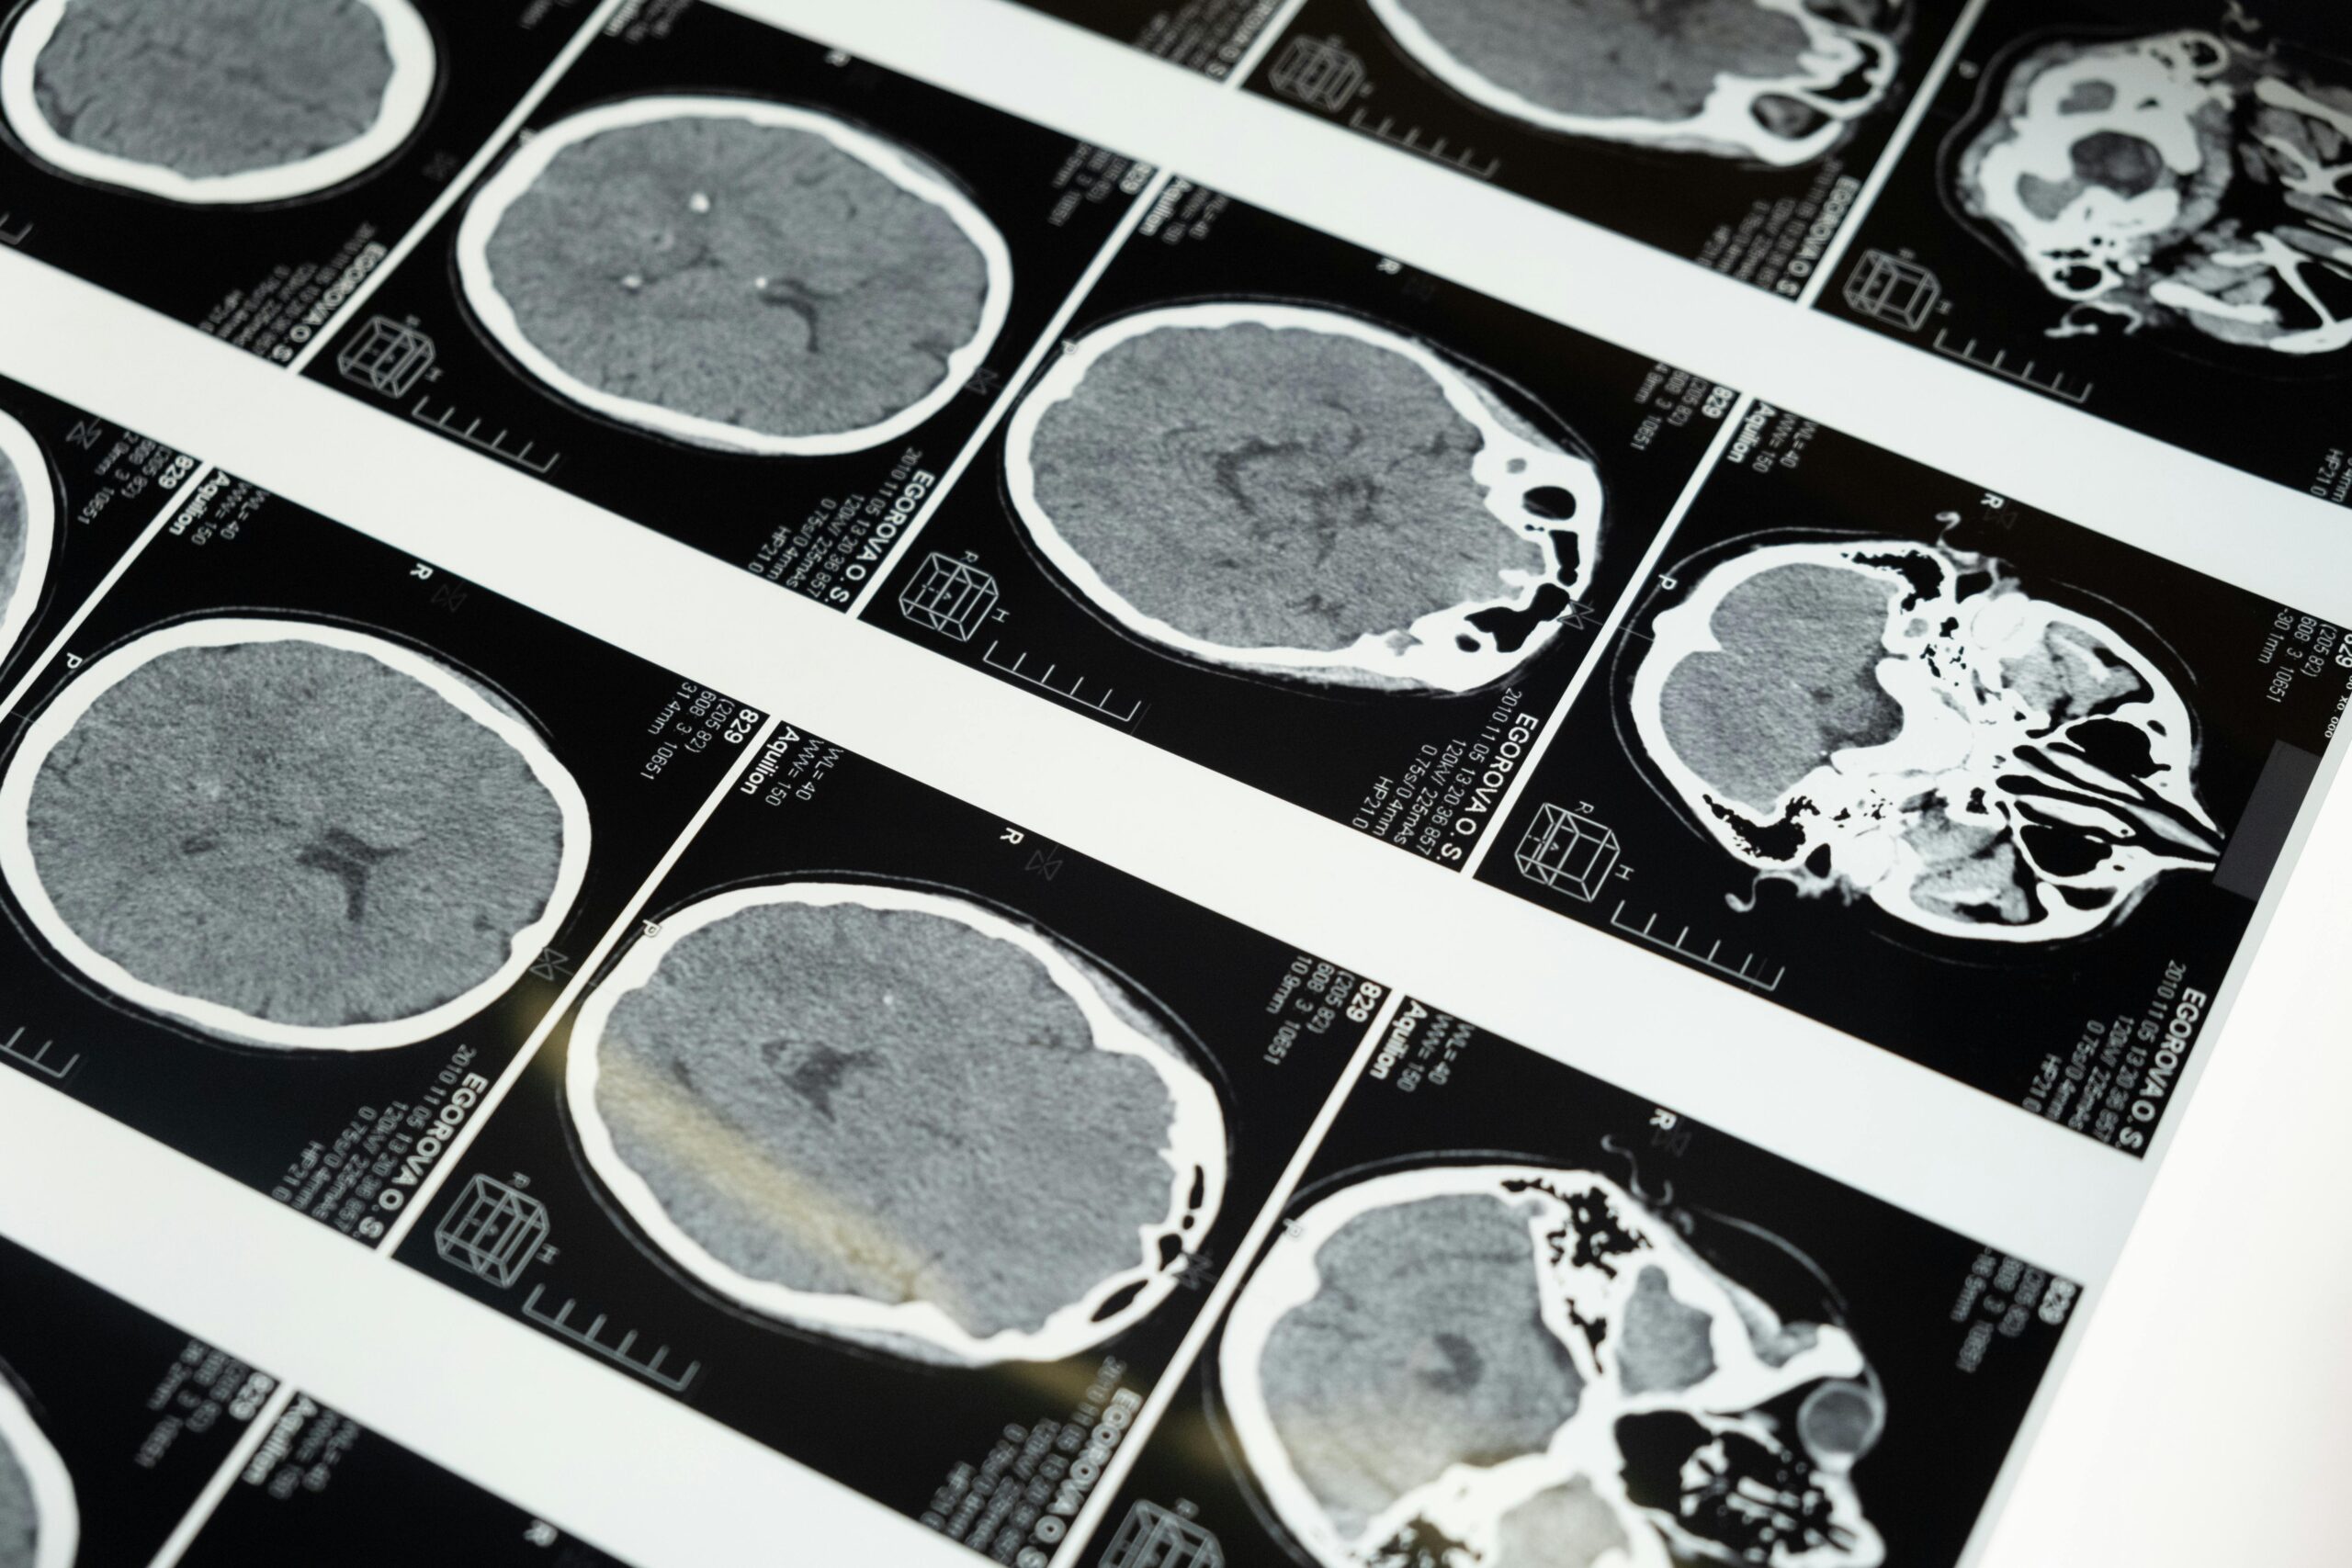

- Advanced Brain Imaging

Get accurate insights into your brain and nervous system health. Our advanced neurology tests ensure early detection and effective care. Expert analysis, fast results, and patient-focused service—every step of the way.